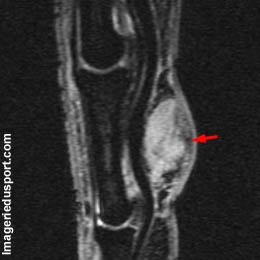

A - IRM du doigt, coupe sagittale T2. Formation tissulaire en hypersignal relatif, au niveau de la face palmaire du doigt.

Tumeur à cellules géantes développée au niveau de la face palmaire du doigt.